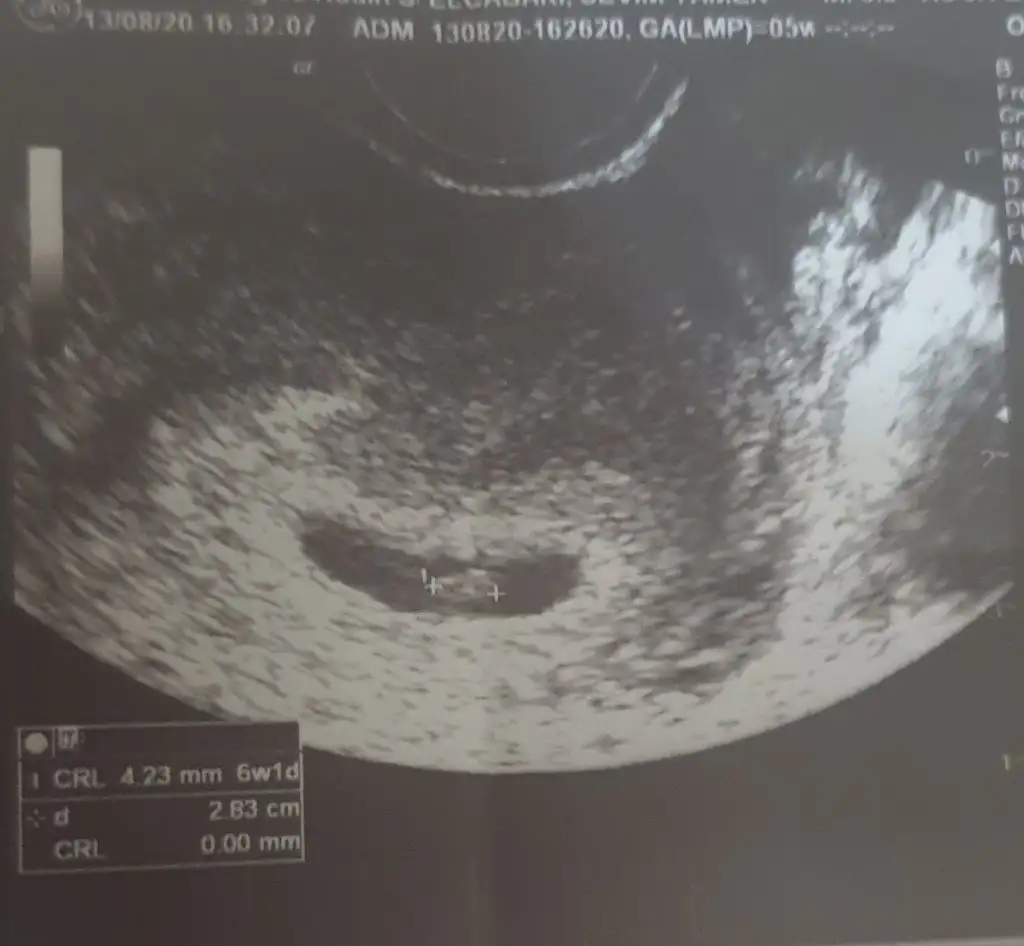

Yaa bende bu fotodan istiyorummkızlar bu benim fasulyemin ilk fotoğrafı ☺

Bebeği görebildi mi doktor bir şey söyledi mi bana söylemedi de ondan soruyorumkızlar bu benim fasulyemin ilk fotoğrafı ☺

çok tatlııııkızlar bu benim fasulyemin ilk fotoğrafı ☺

Masallah sübhanallah..Çok sevindim senin adına sağlıkla ilerlesin hepimizin inşallah..Darısı biz bekleyenlere..Kızlar bugün kontrole gittim çok heyecanlandım. Üstten sadece kese gorunuyordu belli belirsiz, alttan bakabilirim istersen dedi bende kabul ettim. Alttan çok net kese ve bebiş göründü hatta kalp atışı bile belli oluyordu gösterdi bak pıt pıt hareket eden yer bebeğinin kalbi dedi. Çok şükür hersey yolunda. Bir ay sonra gel dedi. Testlerinide aile hekiminden ücretsiz yaptırabilirsin masrafa gerek yok dedi. Doktorumu çok seviyorum,